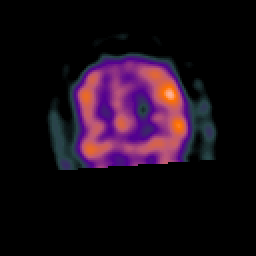

Subacute Stroke, overlay -- Slice #21

[Home][Help][Clinical] Slice 21